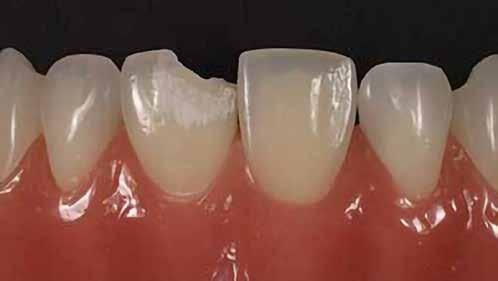

A korábban rutinszerűen használt amalgámtömések mára a legtöbb páciens számára esztétikailag nem elfogadhatóak, hanem fogszínű, természethű restaurációt várnak el. Kaméleon effektussal bíró kompozitokat használva, akár szakavatott szem számára is láthatatlan módon, funkcionálisan és esztétikailag is helyreállítható a fog. Az adhezív technika fejlődésének és az alacsony zsugorodási stresszel bíró kompozitoknak köszönhetően a kiterjedtebb II. osztályú üregek direkt módon is felépíthetőek. Megfelelő protokollokat követve lépésről lépésre kiszámíthatóan elérhető a kívánt végeredmény.

Az 53 éves hölgy páciens jobb felső 6-os fogában látható amalgámtömés cseréje volt a cél. A tömés mellett secunder caries és az amalgám következtében létrejött mesialis zárólécen áthaladó repedés, továbbá mesialis caries figyelhető meg (1. ábra). El kellett kerülni, hogy a tömés kifúrásakor az amalgámtörmelék a páciens szájába kerüljön, esetleg ebből valamennyit lenyeljen, a kezelés első lépésként kofferdám izoláció került fel a jobb felső kvadránsba (2. ábra). A kapocs a 1.7 fogra került, ezzel kényelmesen helyet teremtett a későbbiekben felkerülő matricarendszernek. Az egyszerre több fog izolálása lehetővé teszi, hogy a szomszédos fogak referenciául szolgáljanak a restauráció felépítése közben.

A régi amalgámtömés eltávolítását követően caries indikátor segítette a carieses laesio megfelelő kitisztítását a pulpa expozíciója nélkül. Ezután kerülhetett sor az ideális üregdesign kialakítására, továbbá a zománcszélek finírozására (3. ábra) Az approximális box megnyitása során az alátámasztatlan zománcprizmák eltávolításra kerültek, ezzel is csökkentve a secunder caries képződés veszélyét. Az így kialakuló forma elősegíti a matrica megfelelő adaptációját, végül pedig az approximális box határainak a hozzáférhetőségét, így finírozás során ez jobban kontrollálható és polírozható.